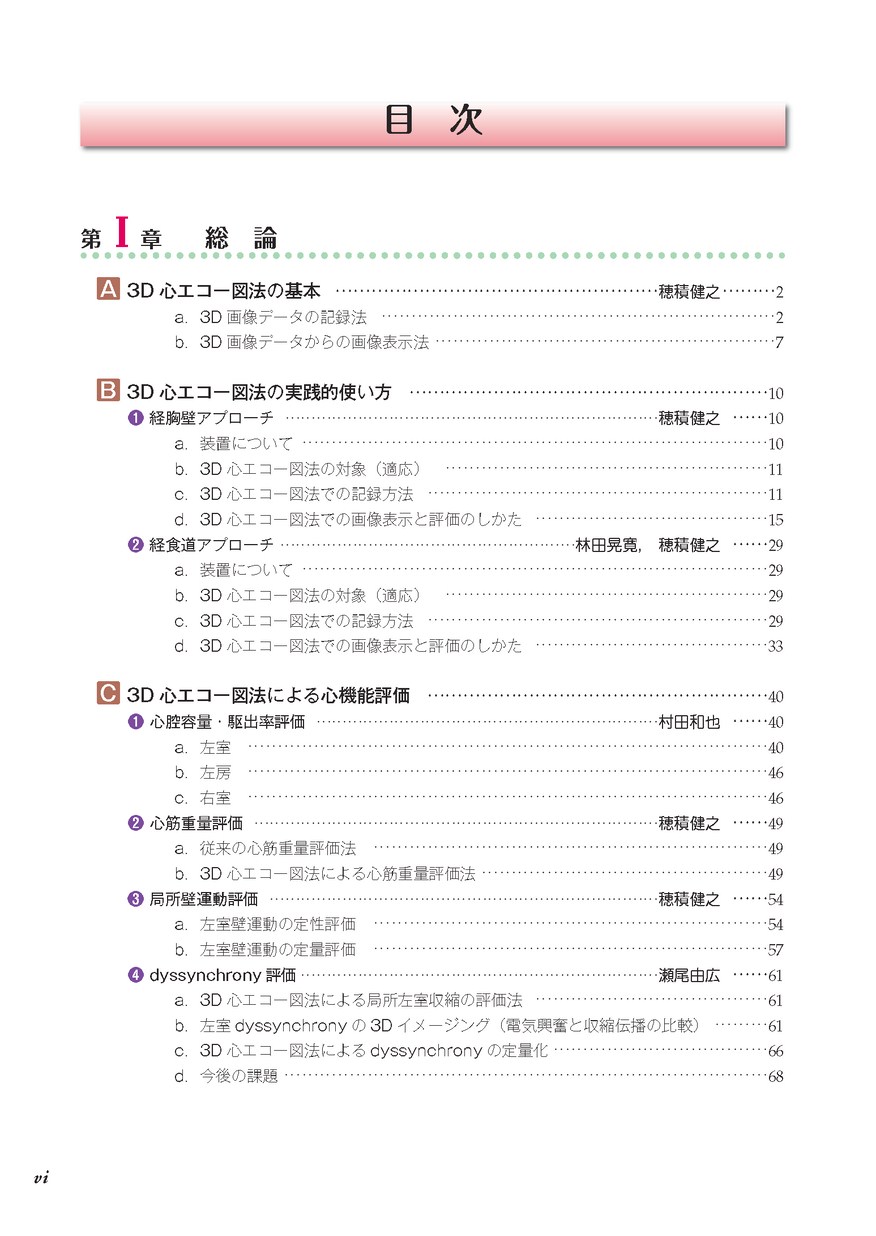

実践3D心エコー図法